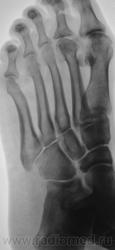

Похоже на болезнь Келлера -2 .

А почему похоже? "Композиторов" иногда не помню, но если асептический некроз головок 2-4 плюсневых костей это Келлер-2, то так и есть.

+ поперечное плоскостопие.

Очень похоже, хотя болеет чаще женский пол!

Только очень старый, сейчас уже просто выраженный артроз.